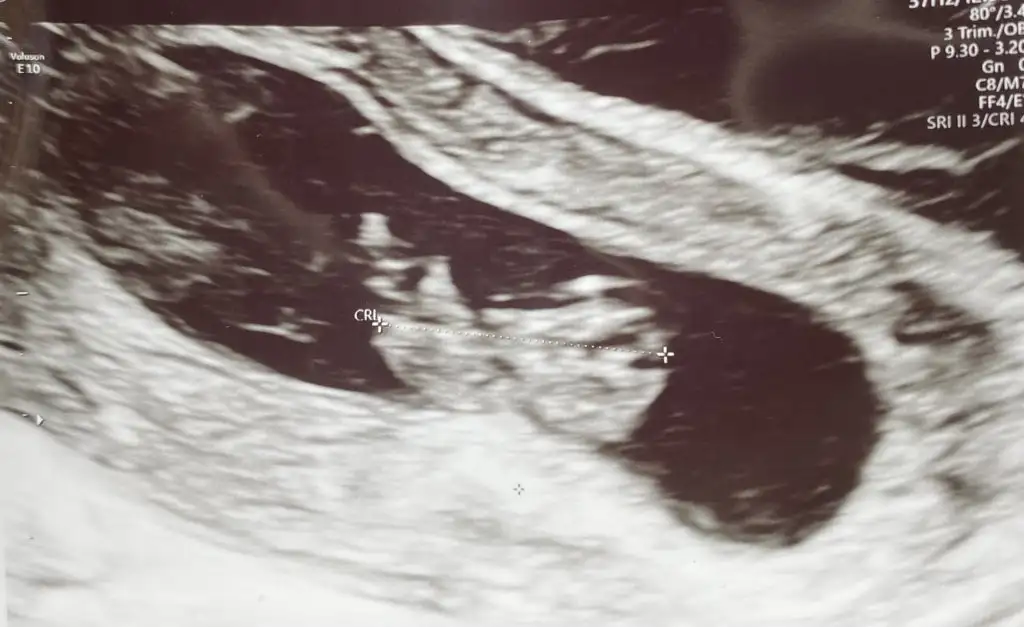

Tahminleri alalım teyzeleri 🫶🏻 9 haftalığız